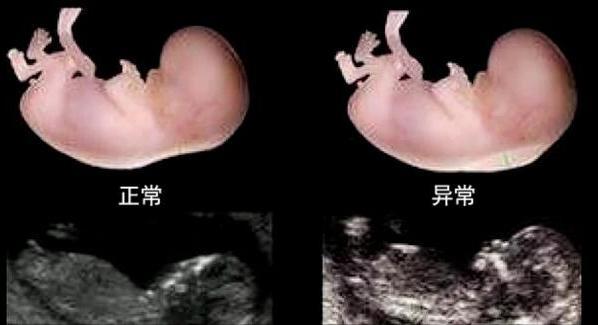

NT检查又称后透明带扫描,是用b超测量胎儿颈部皮下无回声透明层最厚处,评估胎儿是否可能有唐氏综合征的方法。

颈项透明层越厚,胎儿异常的概率越大。

常用判断指标:NT≥2.5 mm在孕11-14周+孕6天时视为异常。

但nt异常的判断不仅要考虑孕周,还要考虑孕妇的年龄。如果是高龄孕妇(35岁以上),异常值范围要适当放宽。NT增厚越明显,胎儿结构异常和染色体异常的概率越大。但需要注意的是,NT异常的胎儿约有80%-90%是一过性病变,最终结果是正常的。